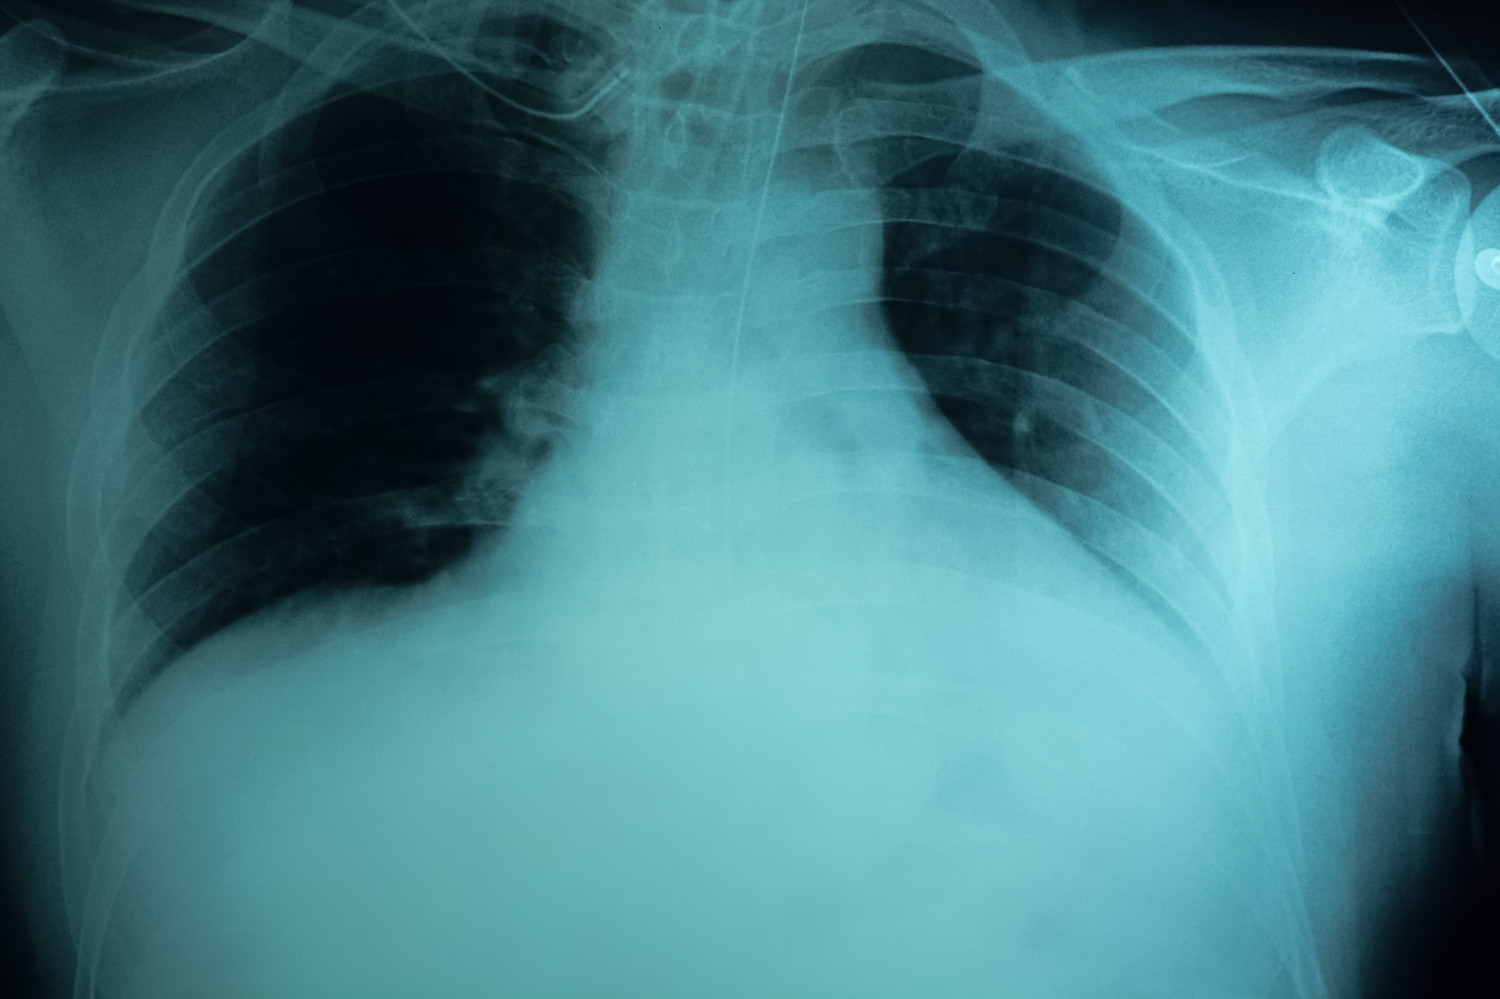

В настоящее время отсутствуют рекомендации по измерению уровня утечки воздуха, размера пневмоторакса или продолжительности симптоматики для прогнозирования течения заболевания на раннем этапе. Обнаружение при рентгенографическом исследовании крупной буллы (>2 см) может указывать на более высокий риск развития рецидива в будущем, однако имеющихся данных недостаточно для рекомендации проведения компьютерной томографии всем пациентам.